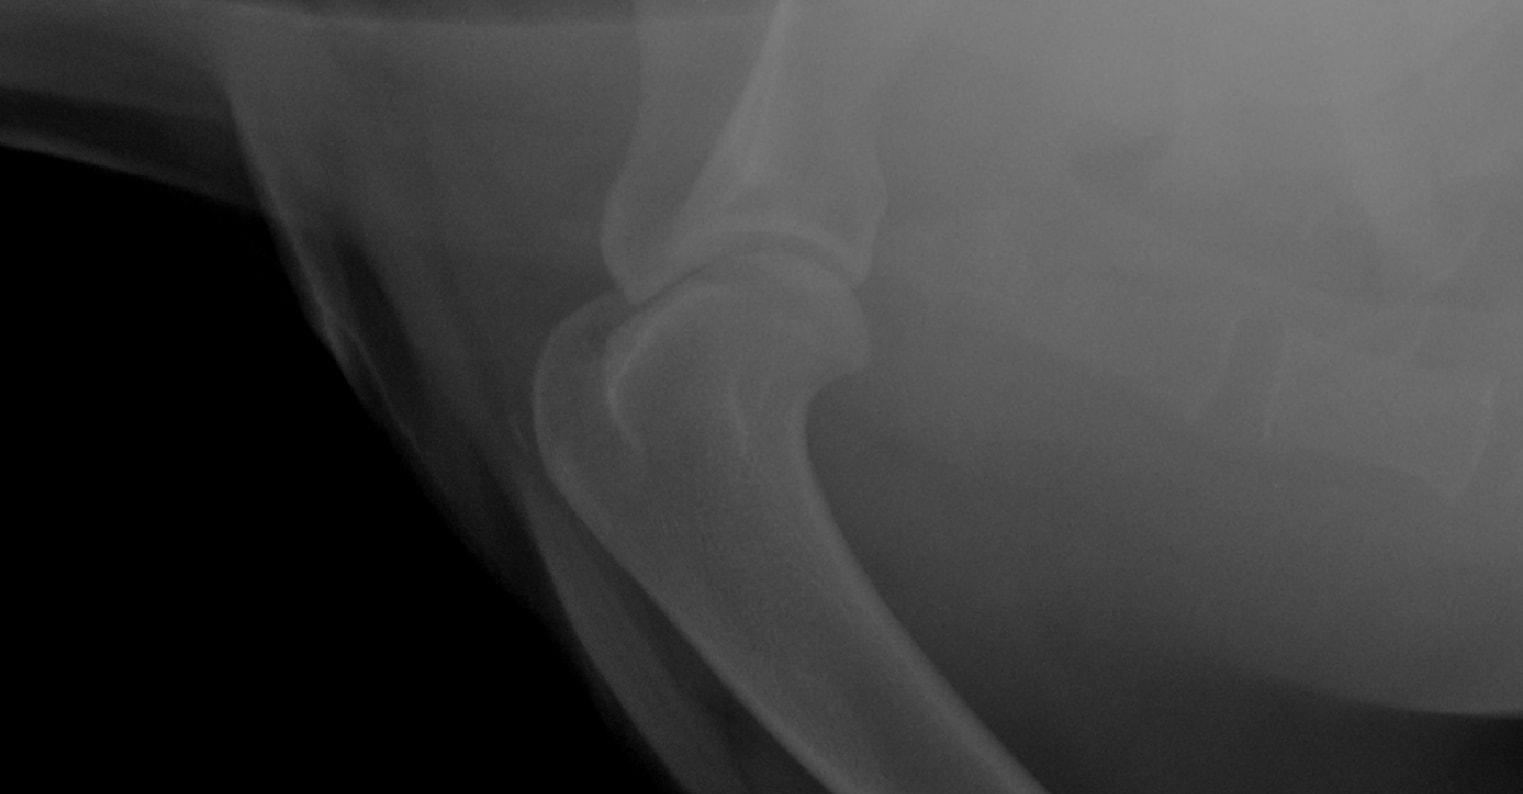

Hi, My Rottweiler is 4 years old. 10 days ago he starting experiencing excruciating pain in is right front leg. we took him to the vet where they took XRays and said he has some inflammation and looks like arthritis. They didn't do much and put him on anti inflams. its been 10 days and made no difference. I have the Xrays attached. Please help so that I know where to send him for proper help.

Hello, sorry to hear about Baloo. His elbows definitely show signs of arthritis. Elbow arthritis is common in Rottweilers has 3 components to it. 2 of these components, a fragments coranoid process and an ununited anconeal process can cause moderate to severe pain. The therapy for this disease includes surgery to remove the chipped bone fragments in the joint. You should consult with an orthopedic surgeon regarding Baloos elbow disease so that his problem can be addressed. In the mean time, you can ask your veterinarian for additional pain meds to try and help keep Baloo as comfortable as possible. Hope this helps and best of luck